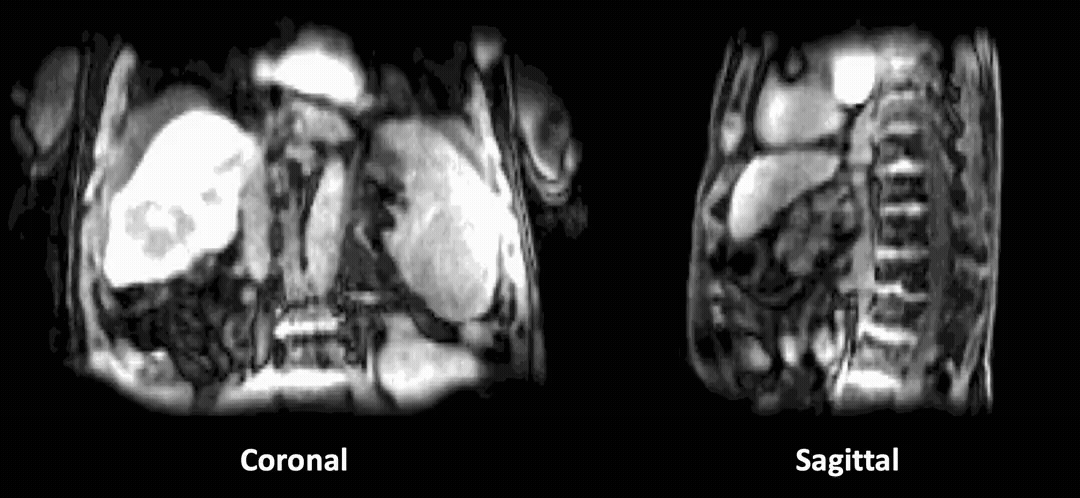

Single-Spoke Motion-Compensated Dynamic

3D MRI Reconstruction via Neural Representation

Lixuan Chen, James M Balter, Liyue Shen, Jeong Joon Park

MICCAI 2025